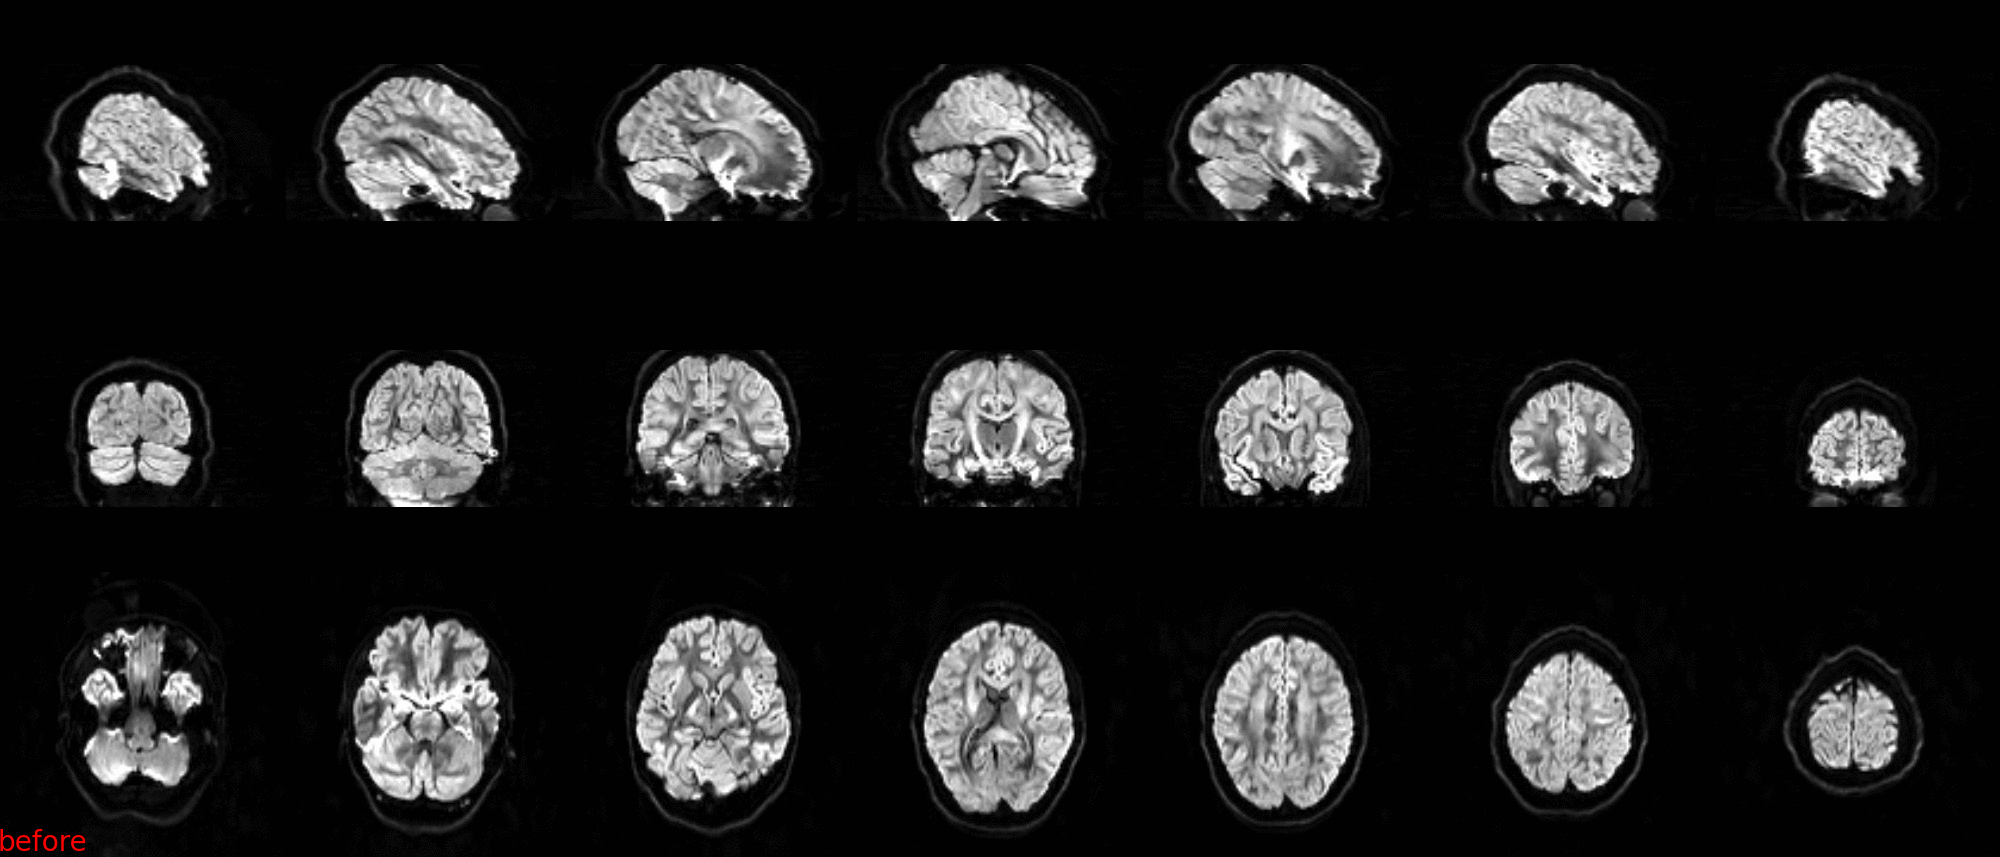

4 steps

- Preparation

- Preprocessing

- Reconstruction

- Outputs